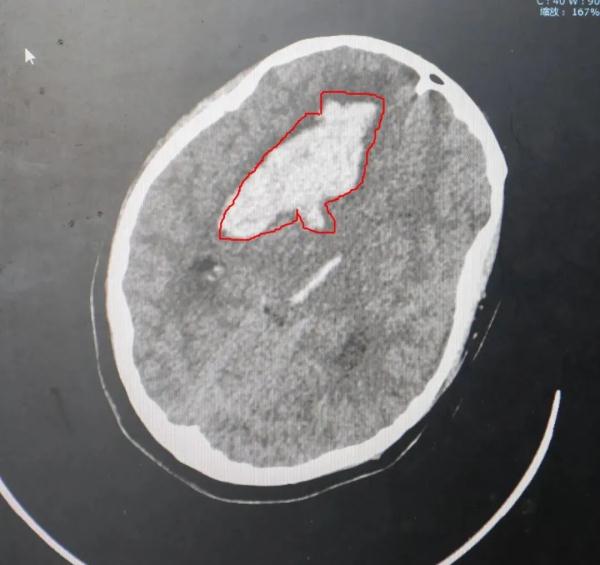

“孩子的情况非常危险,意识不清,双侧大脑半球脑组织肿胀,右侧瞳孔散大。头颅CT提示右侧额叶、放射冠及基底节区出血破入脑室。”

红圈内为颅内血肿

根据CT影像中血肿大小

方震评估孩子

脑出血量应该在40-50毫升左右

且已出现脑疝危象